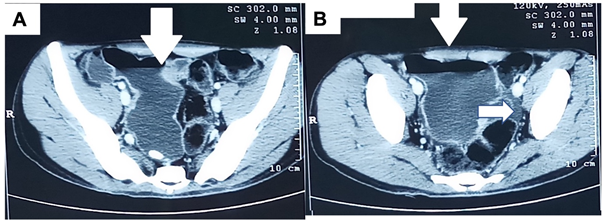

Most common congenital anomaly of the gastrointestinal (GI) tract is Meckel’s diverticulum (MD)- a true diverticulum of ileum. The incidence is 2% among autopsy series; however, only 2-4% become symptomatic.1,2 It may present with crampy abdominal pain, intestinal obstruction (common in adults), or lower GI bleeding (common in children).3,4 Symptoms overlap with tuberculosis, and often create a diagnostic dilemma, especially in regions endemic for tuberculosis. Anti-tubercular treatment (ATT) is usually introduced based on clinical suspicion and imaging features. A rare case of tuberculosis of Meckel’s diverticulum presenting with perforation peritonitis was reported by Rahangdale et al., which was managed by resection and anastomosis.5 We herein, report a case of a young boy, who presented with overt lower GI bleeding and central abdominal pain. Imaging (contrast enhanced computed tomography- CECT) revealed a dilated segment of distal small bowel (Figure 1). He was started on ATT based on clinical suspicion and positive Mantoux test to which his symptoms responded. However, lower GI bleed recurred one year later and was referred to surgical gastroenterology for re-evaluation. Gastroduodenoscopy, colonoscopy and capsule endoscopy was unyielding. Repeat CECT revealed a similar picture. He was taken up for exploratory laparotomy with plan of intra-operative endoscopy. Resection and anastomosis was done for a Giant Meckel’s diverticulum (GMD) discovered intra-operatively. Patient remained asymptomatic for more than 2-years follow-up.

An eighteen years old boy presented with history of hematochezia 3.5years back. Volume was 200-300ml fresh blood/day, for 2-3days associated with postural hypotension. He required 4 units packed red blood cell (PRBC) transfusion. His upper gastrointestinal endoscopy was normal. Colonoscopy revealed mild erosive proctitis and grade-I internal haemorrhoids. Capsule endoscopy, after 11 hours of observation showed multiple ulcers and stricture at 1.20 hours and 9.05 hours from ingestion. Capsule was stuck at the initial stricture site for few hours. CT enteroclysis showed a dilated small bowel loop in pelvis and multiple enlarged lymph-nodes in the mesentery (largest short axis diameter was 11mm) (Figure 1). There was minimal ascites. Mantoux test was positive. India being an endemic country for tuberculosis with more than one-third infected with Mycobacterium tuberculosis, he was started on ATT based on clinical suspicion. He fared well for 10months. He gained 5kilograms of body weight. Two months after completion of treatment, he developed progressive weakness and easy fatigability. No positive history of hematochezia or melena was present. He was pale with a body mass index of 17.3kg/m2. Abdominal examination was unremarkable. Haemoglobin was 7.5g/dl. Fecal occult blood test was positive. Repeat upper and lower GI endoscopy were normal. Triple phase CT again showed a similar dilated small bowel loop in the pelvis (diameter 8.6cm) with air fluid levels and multiple sub-centimetric mesenteric lymph-nodes (figure 1). Suspecting tubercular stricture or intestinal duplication, he was planned for exploratory laparotomy. A dilated Meckel diverticulum of dimeter 10cm at the antimesenteric border of ileum 2 feet from ileo-cecal junction was found, resected using stapler and side-to-side hand sewn anastomosis was fashioned (Figure 2). Biopsy showed intestinal diverticulum with heterotropic gastric mucosa and lymph-nodes showed reactive hyperplasia. He has remained asymptomatic for more than two years of follow-up.

Figure 1 Contrast enhanced CT scan. A & B - showing dilated bowel loop in pelvis (vertical arrow), B- ascites (horizontal arrow).